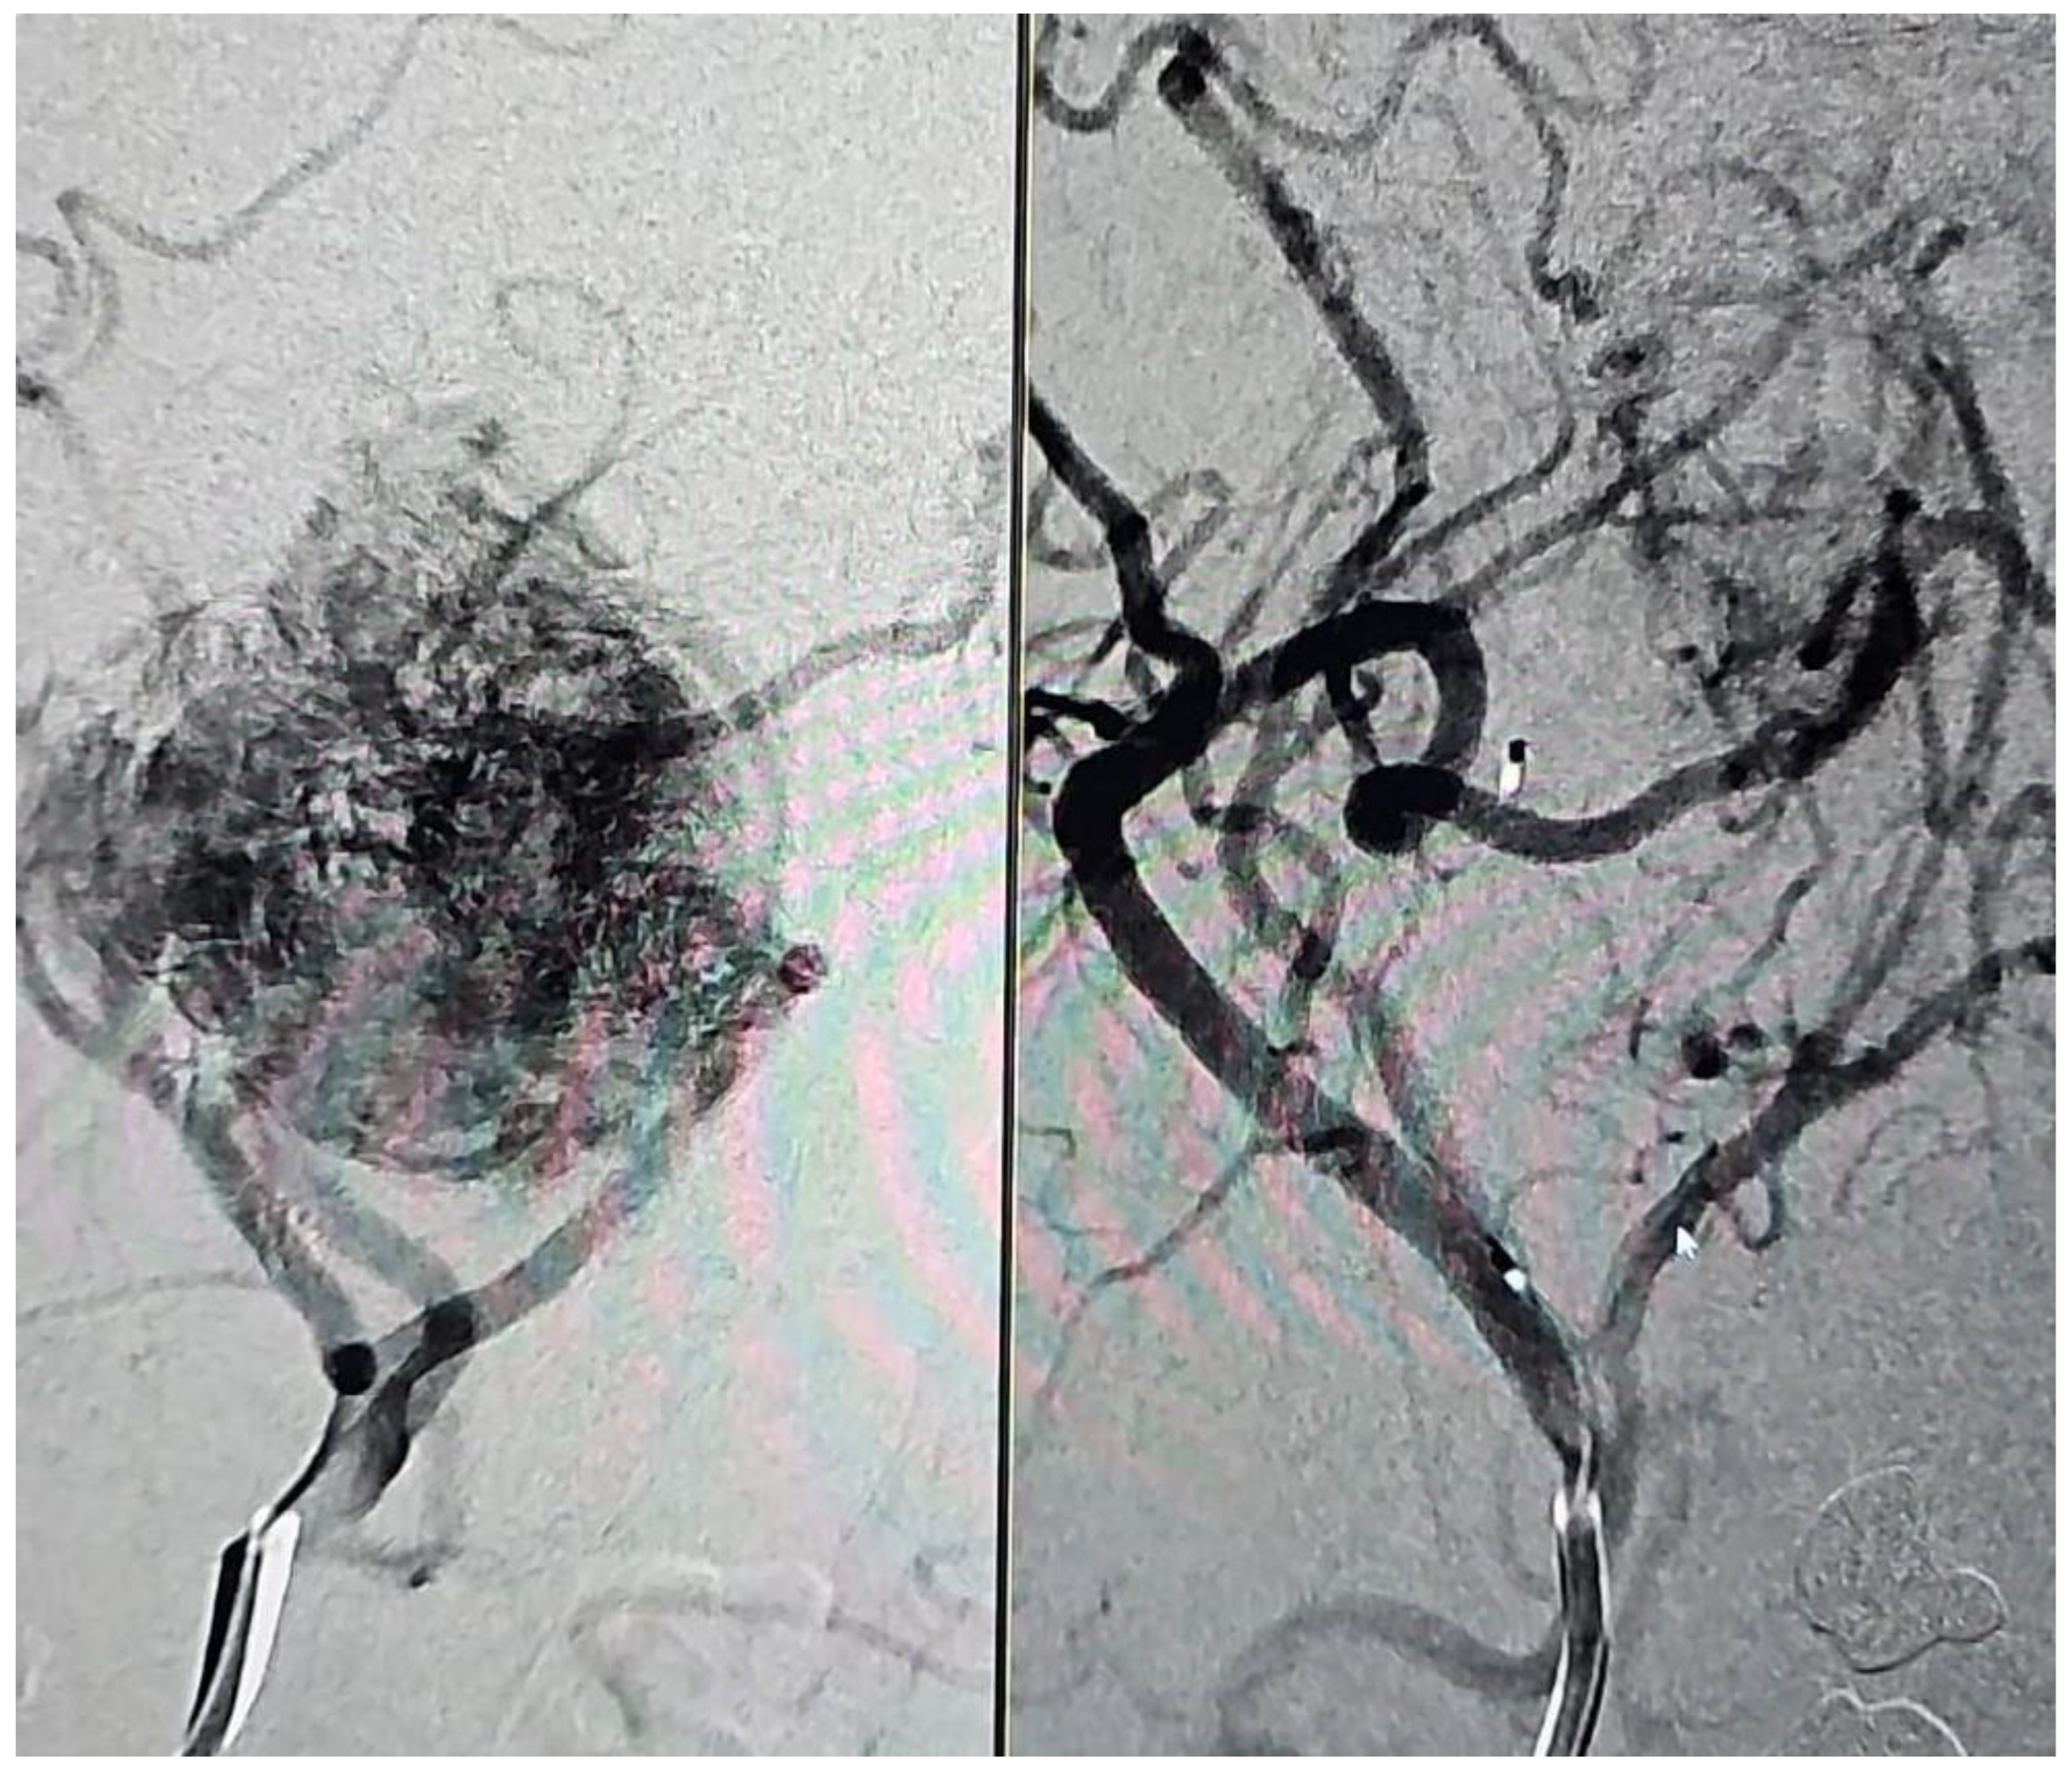

1. Introduction

2. Methods

2.1. Data Collection

2.2. Interdisciplinary Approach

2.3. Embolization Procedure

2.4. Angiographic Evaluation

2.5. Outcomes